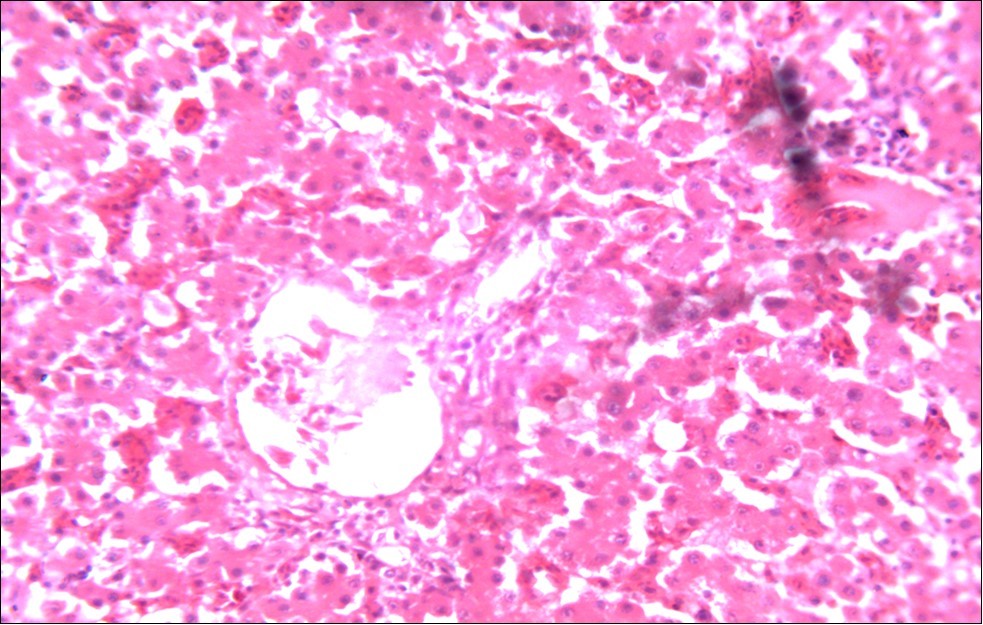

In this study, the reduction in oocyst count observed in the treated group was compared with amprolium could be attributed to the presence of a bioactive compounds azadiractin A which is known to bind membrane cholesterol, altering the integrity of the parasite membrane, resulting in loss of homeostasis and eventual death of the parasite 29]. Also, limonoids contained in NeemAzal® inhibit protein digestion and uptake of vitamins and minerals by the parasites in the gut 17. This action results in impaired nutrient utilization, reduced growth, and multiplication of the parasite which could contribute to the reduced oocyst count observed. Extracts of neem and mahogany when used individually have been reported to reduce oocyst count in avian coccidiosis 11,12. The observed reduction in oocyst count and the significant increase in weight gain of the birds when treated with NeemAzal®, as compared with the negative control group could probably be due to the inhibition of inflammation in the intestinal mucosa which is suggestive of an increased nutrient absorption across the intestinal wall and enhanced feed conversion ratio compared to the negative control this is in agreement with reports by Nwosu et al.12 and Biu et al.11 who also reported an increased weight gain and feed conversion ratio in birds treated with only Khaya senegalensis extracts and Azardiractaindica, respectively. The observed increase in RBC and haemoglobin concentration is indicative of the erythropoieticability of the NeemAzal®, which is beneficial since the Eimeria parasite in the epithelia of the intestines causes bloody diarrhoea and consequently anaemia (Table 1). This finding is in consonance with 15 who reported an anti-anaemic effect of Khaya Senegalensis on phenyl hydrazine-induced anaemia in rats. Neem has been shown to possess anti-anaemic properties in rats 14. The significant increase in mean weight gain in treated birds when compared to the negative control is possibly due to the inhibition of inflammation in the intestinal mucosa which is suggestive of an increased nutrient absorption across the intestinal wall and enhanced feed conversion ratio compared to the negative control. Nwosu et al.12 and Biu et al.11 reported an increased weight gain and feed conversion ratio in birds treated with only Khaya Senegalensis andAzadiractaindica extracts, respectively. In a similar study, Neem acts like toltrazuril exhibiting anticoccidial. In addition, exposure of broiler chickens to 20000 Oocysts of Eimeria tenellacaused generalized degeneration of the caecal glands with massive Oocysts and gametocyts within the caecal glands with fibrosis (Figure 3, Figure 4 & Figure 5), however, broiler chickens treated with NeemAzal® post exposure to 20000 Oocysts of Eimeria tenella, shows equal numbers of caecal tissues with non-observable histopathological lesions (Figure 4), possibly due to the antioxidant and anti-coccidian effects of NeemAzal®. The exact mechanism of action of neem against coccidian parasites is unknown, but a report by the National Research Council 1992 30, suggested that aqueous neem leaf extract, when taken orally, produces an increase in red cells, white blood cells and lymphocyte counts thus enhancing the cellular immune response, increasing antibody production and so most pathogens can be removed before they cause the symptoms associated with disease this was in agreement with this study as seen in Table a remarkable increase of the RBCs.

In addition, the generalized degeneration of the caecal glands, moderate numbers of gametocytes within the glandular regions with fibrosis which underscores reparative process in response to injury evoked by coccidiosis in the chicks which was perhaps brought about by the antioxidant and chemotherapeutic effect of NeemAzal®. The observed increase in RBC and hemoglobin concentration (Table 1) is indicative of the erythropoieticability of NeemAzal®, which is beneficial since the Eimeria parasite in the epithelia of the intestines causes bloody diarrhea and consequently anaemia. This finding is in consonance with 15 who reported an anti-anaemic effect of Khaya senegalensis on phenyl hydrazine-induced anaemia in rats. If the results of this study are juxtaposed with the results of the previous studies on potent antioxidant, hepatoprotective and mitigative role of methanolic extracts of Azadirachtaindica,in both natural and experimental infection with Eimeria species and can be deduced that, NeemAzal® could be said to be a potent antioxidant, chemotherapeutic and tissue protective agent. This study also answered a question on further study advocated to determine the maximum safe levels of neem supplementation because the higher doses, due to its bitterness, may show adverse effects on feed intake which will change the performance parameters of birds (Figure 6 and Figure 7) . Light microscopic inspection of hematoxylin and eosin-stained sections revealed that the epithelial cells of the Cecum were infected by E. tenella(Figure 3 and Figure 4). The results of the safety study showed that exposure of chickens to NeemAzal® at 200mg/kg body weight did not alter the histoarchitecture of liver and kidney (Figure 6 & Figure 7) which is similar to the work conducted in the same environment by a group of Scientists 34. It is therefore recommended that NeemAzal® could be used as a coccidiostat to replace the expensive anti-coccidiostats in the market.

Figure 6.Photomicrograph of liver of chick administered NeemAzal® at 200 mg/kg showing no observable lesion X250 (H & E)